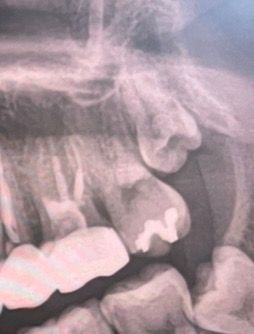

사랑니 발치 대학병원 가야 하는지 봐주실 수 있나여

상악 사랑니가 2개 나고있다고 빼는 게 좋겠다고 진단받았는데요

이거 매복인가요?? 대학병원 가는 게 좋을까요?

• 1번 째 사진

사진에 보이는 정도는 매복사랑니 입니다. 크게 어렵지는 않는 발치라서 크게 걱정하지 않으셔도 될것같습니다.

사랑니 발치 진단을 받으셔서 걱정이 많으시겠어요 치근단 사진으로 보아 현재 상태는 매복치아 입니다 하지만 위치나 방향으로 봤을 때 엄청 위험하거나 어려운 정도는 아닙니다 집 근처에 치과대학중 구강 악안면외과 인턴, 레지던트 수료하신 분 있으시다면 그분한테 받아도 무관할거 같습니다 너무 걱정마시고 만약 그부분이 발치 어렵다고 하시면 그때 대학병원 가시면 될거 같습니다

아직 맹출중이몀 20대 중반까지는 더 사랑니가 내려오고 나서 뽑아도 됩니다 지금 발치가 급한건 아닐것 같네요